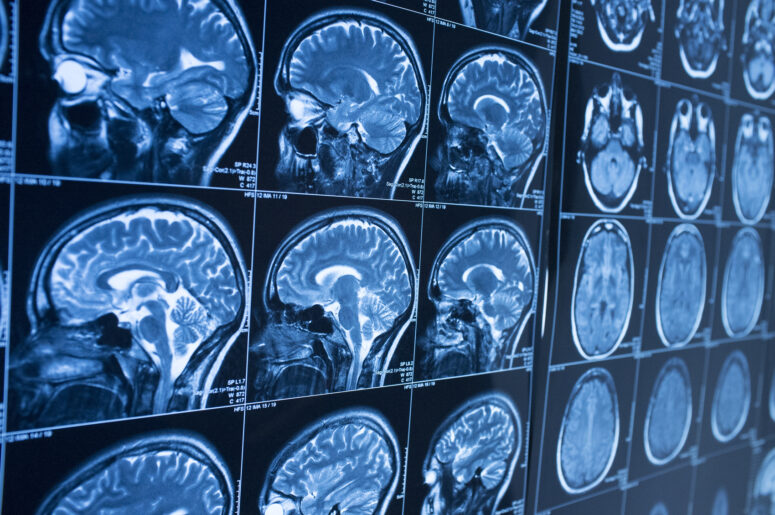

Traumatic brain injury is one of the leading causes of deaths in the country. Whether the cause is a motor vehicle accident, a fall or a sport injury, a violent blow to the head can result in a concussion, which can, in turn, lead to a serious disability or even death. Brain injury treatment does not guarantee full recovery. In some cases, a victim needs long-term care. Readers in New York may be interested in some recent findings regarding traumatic brain injury in football players.

Brain diseases — such as chronic traumatic encephalopathy, a degenerative brain disease that is caused by repeat brain trauma and concussion — are common among football players, boxers, wrestlers and hockey players. CTE in particular has been sensationalized by the recent suicides of several retired professional football players who had been diagnosed with CTE.

In an ongoing effort to study brain disease, medical researchers examined the brains of 36 deceased athletes. Posthumous diagnoses indicated that 22 of the athletes experienced mood and behavioral problems as a first indication of CTE and that 11 of them had difficulties with thinking and memory. The remaining three did not show any symptoms. Patients in the mood and behavioral group tended to be more violent, both verbally and physically, compared to patients who had thinking and memory symptoms. Depression is another sign of the disease.